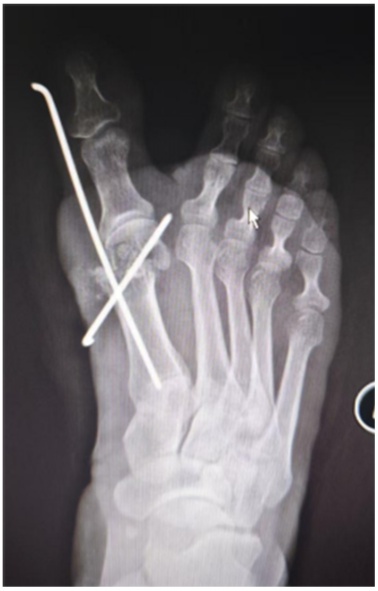

患者女,46岁。因“右足进行性行走疼痛、伴踇趾外翻畸形8月余”来我科就诊。专科检查:右侧第一跖趾关节外翻畸形(见图1(a)图1(b)),活动受限,拇囊部位压痛明显,无纵向叩击痛。第一跖趾关节松弛,活动后疼痛加重。前足功能AOFAS评分为45分,神经血管检查正常,其余肢体未见异常。既往史无特殊,检验结果未见异常。右足部X线片显示:右侧第一跖趾关节对位欠佳呈外翻改变,外翻角约33˚,第1、2跖骨间夹角约为9˚,第一近节趾骨近端可见骨质增生边尖(见图1(c))。入院诊断:右足拇外翻合并第一跖趾关节半脱位。完善相关检查后,行右足拇外翻切开截骨矫形克氏针内固定术。手术过程:麻醉生效后,患者取仰卧位,绑止血带,右下肢常规消毒铺巾,打止血带,C臂透视确认截骨位置,截骨位置靠近跖骨颈的内侧隆起处。皮肤切口:取右足背内侧第一跖趾关节处纵切口,切一长约2 cm皮肤切口。操作过程:电刀分离皮下组织至关节囊,电凝止血,切除增生关节囊,显露内侧跖趾关节,用摆据距跖骨远端2 cm处垂直于跖骨干横向截骨,将跖骨头向外侧推移,将第1根金属骨针沿远端截骨断端前内侧皮下置入并从拇趾趾甲近端内侧皮缘穿出,将布巾钳插入跖骨截骨近端髓腔,再从拇趾趾甲内侧将金属骨针置入跖骨干髓腔基底部内固定,透视确认足拇外翻畸形矫形满意,将第2根金属骨针从跖骨内侧缘距离跖骨近端截骨面1 cm处上斜形插入,从远端截骨面中点穿过,从跖骨远端外侧皮质穿出(见图1(d)图1(e)),固定截骨远端,C臂透视见拇外翻纠正,内固定位置可(见图1(g))。逐层缝合切口,以敷料固定包扎保护拇趾于中立位(见图1(f)),术后第2天复查X线(见图1(h))。术后6周来院拆除第2根金属骨针后,复查X线示恢复可(见图1(i)),术后7周来院拆除第1根金属骨针,复查X线片示恢复可(见图1(j)),术后3月我院复查足部情况(见图1(k))。

(a) (b) (c) (d)

(e) (f) (g)

(h) (i) (j) (k)

(a) (b) 术前右足外观;(c) 术前片X线片:右足中度拇外翻并第一跖趾关节半脱位;(d) 术中克氏针固定位置;(e) (f) 皮肤切口:右足背内侧第一跖趾关节处纵切口,切一长约2 cm;(g) C臂透视确认脱位复位满意,内固定位置可;(h) 术后右足正侧位x片显示:第一跖趾关节对位良好,跖骨断端对线可,轻度向内移动约1/4;(i) 术后6周患者右足部X线复查情况;(j) 术后7周右足部X线复查情况;(k) 术后3月右足部复查情况。

Figure 1. Patient’s imaging data

1. 患者影像学资料